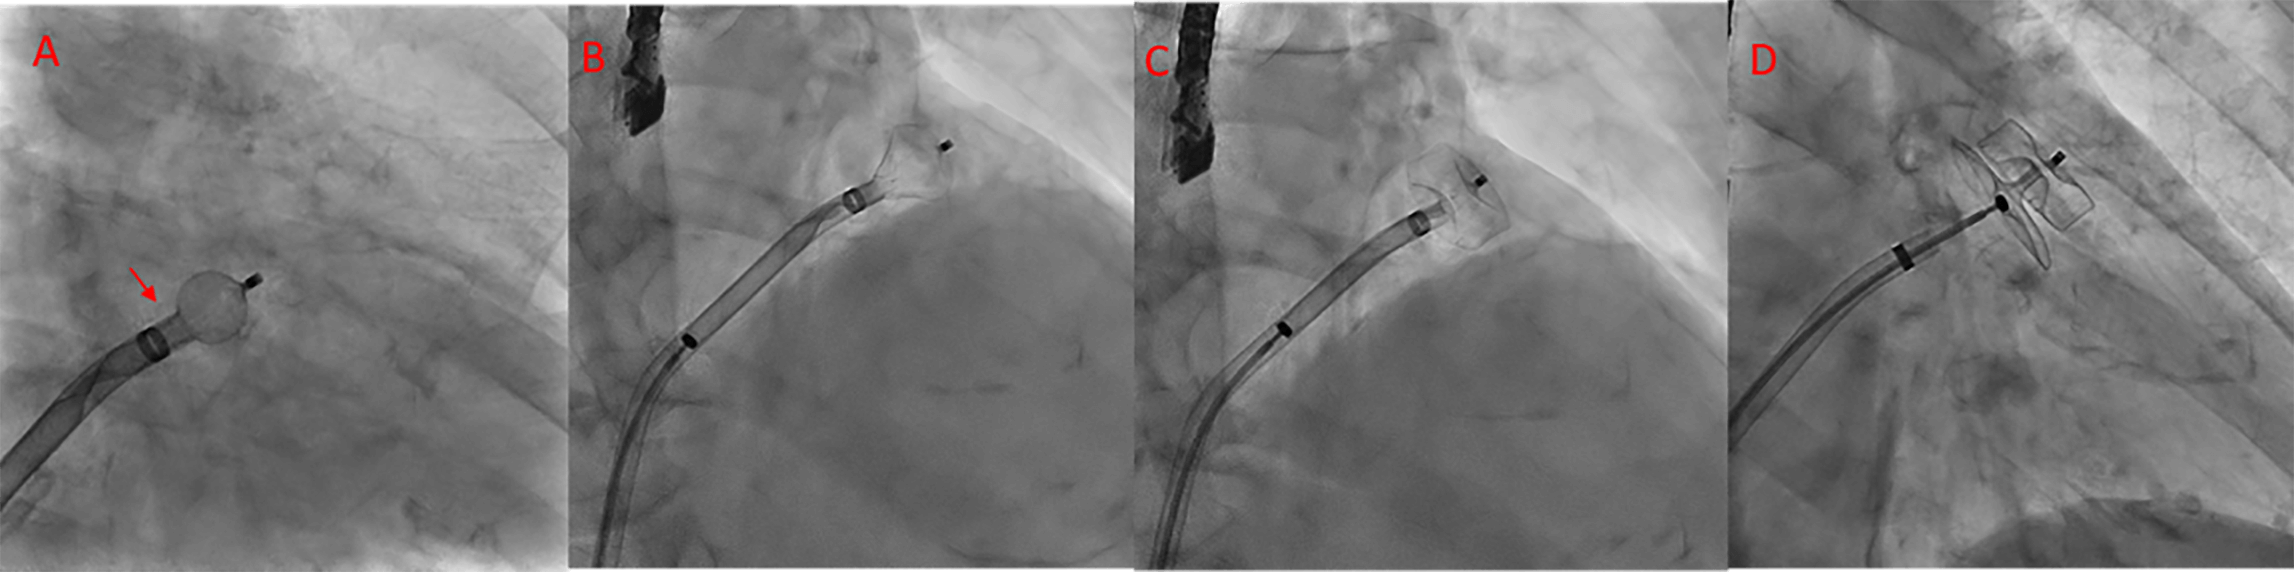

platinum marker wires are distal to the sheath’s radiopaque marker (Fig. 20).

Fig. 20.

Sequence of Amulet device deployment. (A) Spherical configuration; in this position, the device can be safely rotated clockwise or counterclockwise. The platinum markers are located distal to the sheath’s radiopaque marker (arrowhead). (B) Triangular configuration; in this position, the device can be safely advanced. (C) The lobe is fully deployed. (D) Both the lobe and disc are fully deployed.